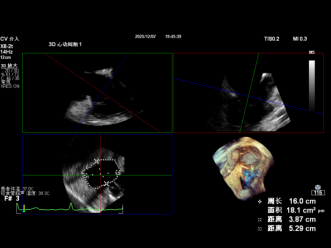

2. Annuloplasty Effect:

- Tricuspid annulus circumference: 20.1cm, area: 31.7cm² (massive tricuspid annulus);

- Septal-lateral diameter: 63mm, antero-posterior diameter: 63mm;